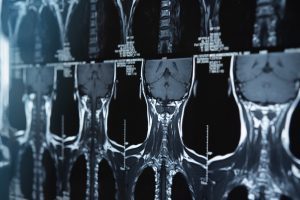

整形外科を受診したらレントゲン撮影のほかにMRI検査も受けるのがおすすめです。

MRI検査はレントゲンでは分からない、筋肉や神経、靭帯などの異常を見ることができます。

まずは医療機関を受診し、レントゲンやMRIで詳しく検査してもらいましょう。